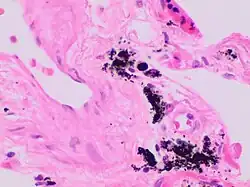

Gandy–Gamna nodules or Gandy-Gamna bodies, sometimes known as Gamna-Gandy bodies or Gamna-Gandy nodules, are small yellow-brown, brown, or rust-colored foci found in the spleen in patients with splenomegaly due to portal hypertension,[1] as well as sickle cell disease. They consist of fibrous tissue with haemosiderin and calcium deposits, and probably form due to scarring at sites of small perivascular haemorrhages.[2] They are visible on MRI scanning due to the presence of haemosiderin.[3]

They can also be seen in atrial myxomas.